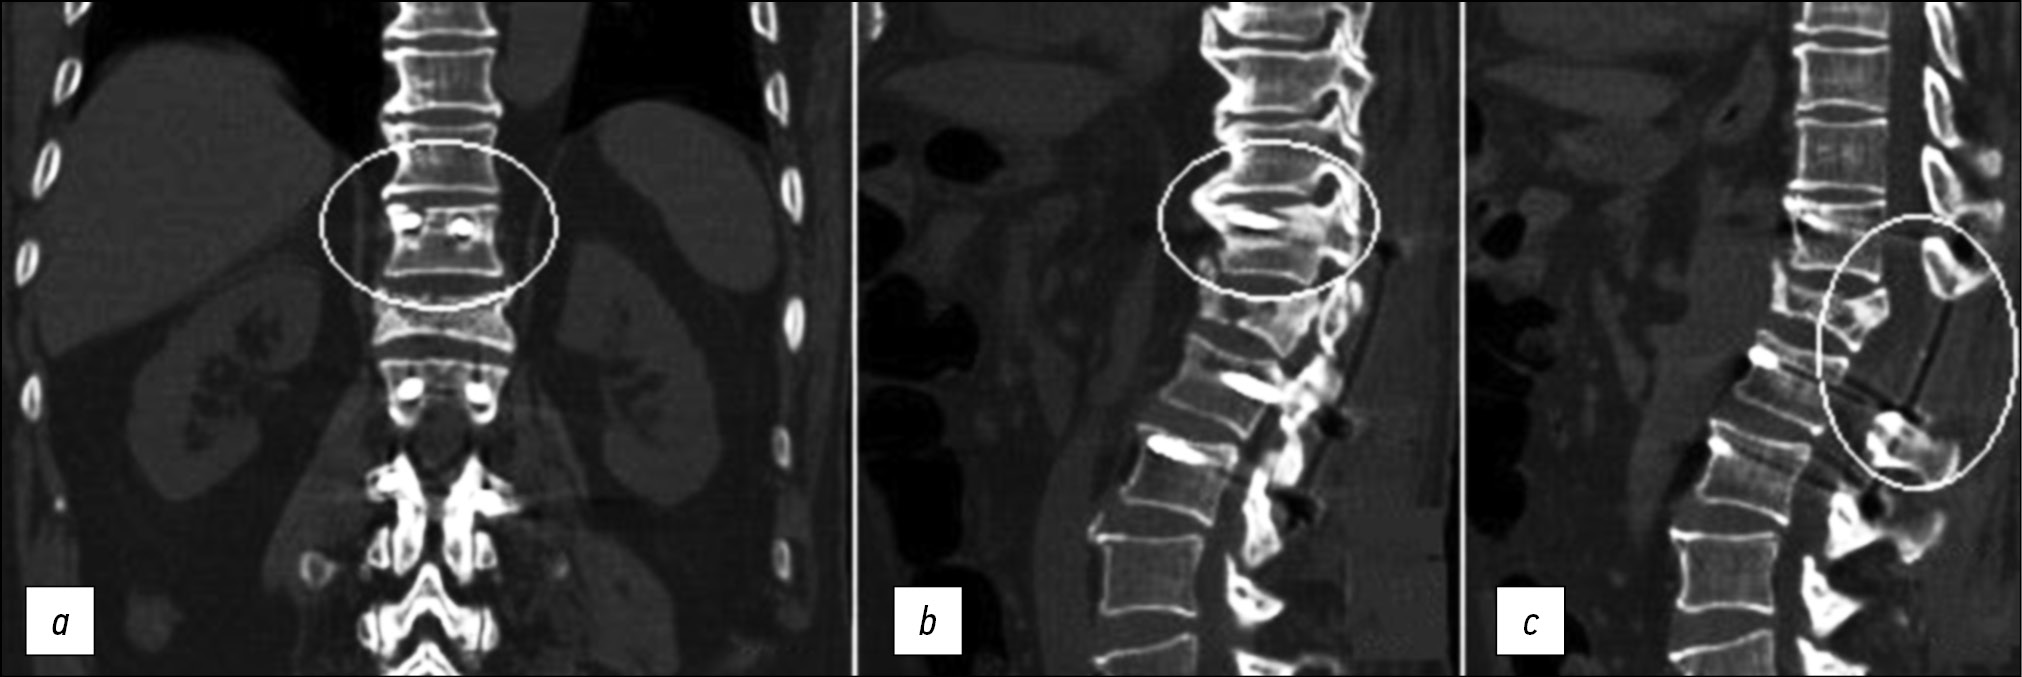

Вокруг винтов в Th11 позвонке (в теле и ножках) отмечали зону резорбции костной ткани шириной 5–9 мм (рис. 2, а). Передние концы винтов мигрировали к верхней замыкательной пластине Th11 позвонка, справа наблюдалась ее перфорация и выстояние импланта в межпозвонковый диск (рис. 2, b). Тело Th12 позвонка клиновидно деформировано, высота его снижена на 1/2. Дорзальные отделы тела позвонка пролабировали в просвет позвоночного канала до 6,5 мм, деформируя дуральный мешок на этом уровне (рис. 2, c). Полноценной консолидации перелома не наблюдалось. На уровне Th12 позвонка визуализировалась зона резекции задних структур позвоночника, которая была представлена остистым отростком, дугой, нижними и верхними суставными отростками Th12 позвонка.

Рис. 2. Компьютерная томография позвоночника больного Е., 71 год, до операции. Пояснения в тексте.